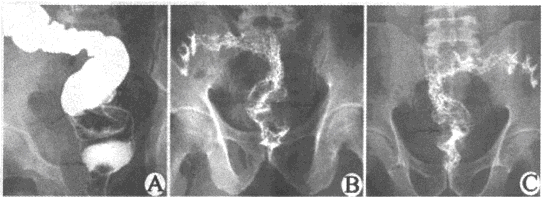

肠结核x线

肠结核x线,

诊断为a,溃疡性结肠炎b,克罗恩病c,肠结核d,结肠癌e,直肠癌

《内科学精品教学课件同济》27肠结核及结核性腹膜炎.ppt

胃肠道常见病影像表现胃溃疡消化道肿瘤肠结核